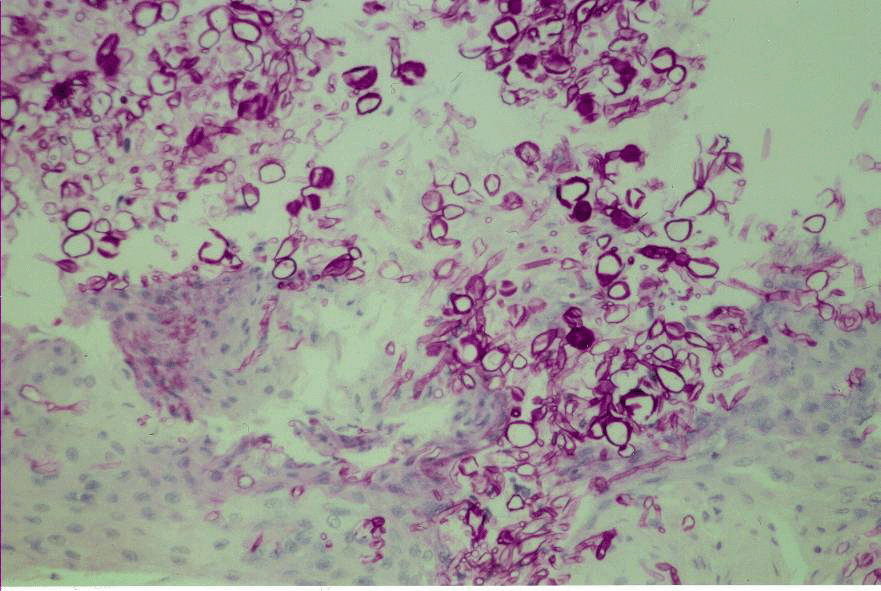

Les examens histologique et microbiologique des biopsies cutan?s r?v?laient la pr?sence du Fusarium moniliforme. La recherche des moisissures s'av?rait positive dans le liquide broncho-alv?olaire, les urines et la moelle osseuse (d?sertique malgr? l'usage des GM-CSF). Les pr?l?vements mycologiques des ongles ?taient n?gatifs. Le traitement par amphot?ricine B et flucytosine, puis par caspofongin ?tait inefficace. Au 66e jour, un traitement par voriconazole associ? ? l'amphot?ricine B et ? des transfusions leucocytaires ?tait instaur?.